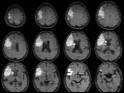

Die Netzhaut: ein Fenster zu Herz und Gehirn: Mit digitaler Fotografie gibt die Netzhaut unseres Auges Aufschluss über den Zustand unserer Herzkranz- und Hirngefäße, denn auch die Netzhautgefäße verändern sich bei Bluthochdruck, sie werden enger und zeigen Gefässwandveränderungen. Diese Veränderungen kann man mit einer "Fundus-Kamera" (Augenhintergrundkamera) fotografieren und einer entsprechenden Auswertung zuführen. Die Verlaufskontrolle zeigt Gefässveränderungen auf. Auf diese Weise erhalten die Patienten sehr schnell einen Hinweis darauf, ob ihre Gefäße bedeutsame "arteriosklerotische" Veränderungen aufweisen.